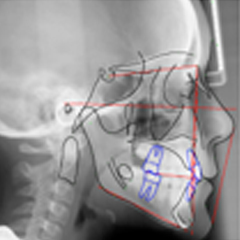

A completa integração com DATABASE do JoeCeph da RMO® propicia ao iSmartOffice uma grande vantagem sobre os demais sistemas de planejamento Ortodônticos.

. Imagens e Cefalometria